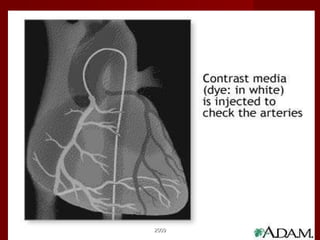

CORONARY ARTERY DISEASE Narrowing or obstruction of one or more coronary arteries as a result of: Atherosclerosis  Arteriosclerosis 2009

2009